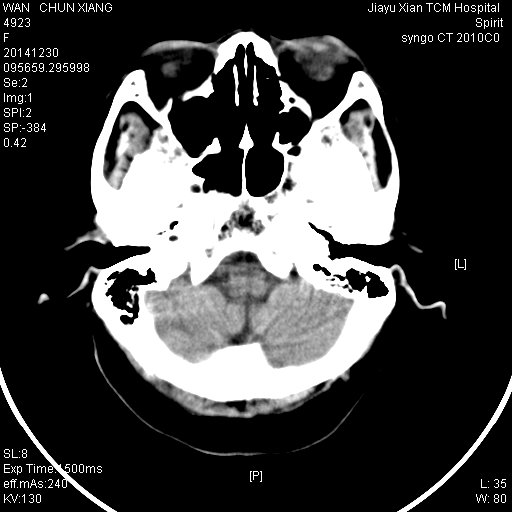

CT49651:女,72岁,因头晕,头痛来诊

)左侧枕叶脑梗塞。2)胼胝体左侧压部腔隙性脑梗塞。3)脑白质病。4)脑萎缩。

1)左侧枕叶脑梗塞。2)胼胝体左侧压部腔隙性脑梗塞。3)脑白质病。4)脑萎缩。

左枕叶梗塞,皮层下动脉硬化型脑病

左枕叶梗塞

1、左枕叶梗塞。

2、脑白质脱髓鞘改变。

左后枕叶梗塞,脑转移待排,建议MRI

皮层下动脉硬化型脑病

左侧枕部低密度灶边缘清晰,占位效应及周围水肿不著,部分区域直达颅骨边缘。考虑梗塞可能。为了小心起见,透视肺部,看看有无肿块,排除转移。

皮层下动脉硬化性脑病。